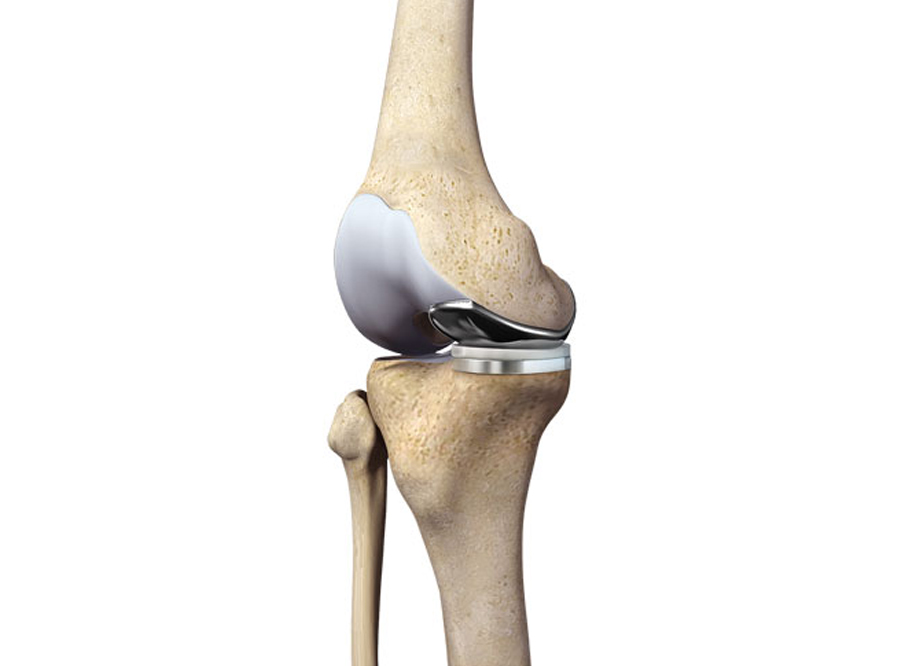

The following are the types of specialised implants designed to fit only the affected part of the knee joint:

The objective is to preserve natural knee joint tissue as much as possible. Therefore, only a few components are used.

Implant selection mainly depends on the following factors: